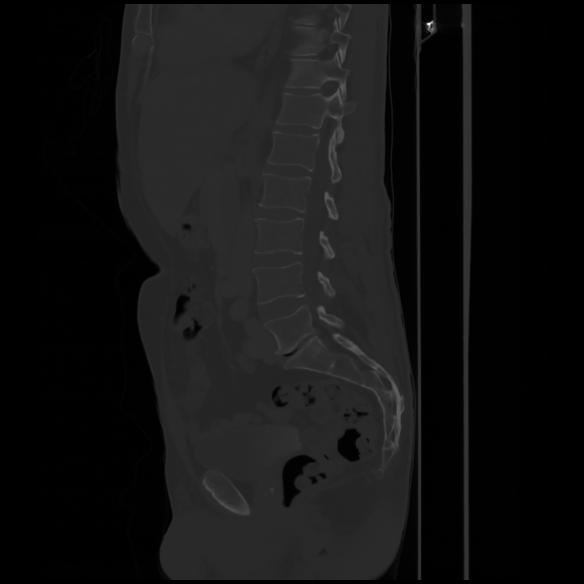

7 CUERPO,CE,Sagittal,3.000,CUERPO,Sagittal,